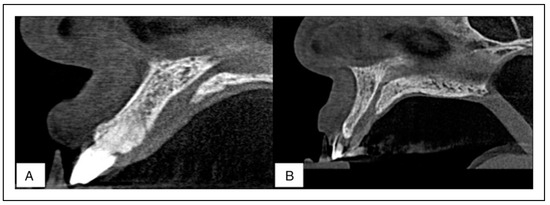

Figure 6. Sagittal CBCT sections of the maxillary bone both the flat (a) and concave (b) shapes encountered in the present study.

As pertain the shape of the maxillary bone, it was classified as either concave, convex, or flat (Figure 6). The results reveal that the flat shape was most prevalent among males while the concave shape was most prevalent among females. No convex shape was encountered in this study. These results exhibited sexual dimorphism (Chi-square test, P <.05). Furthermore, the angulation of the maxillary bone was found to be similar at an average of 116.00° to the horizontal plane in both males and females.